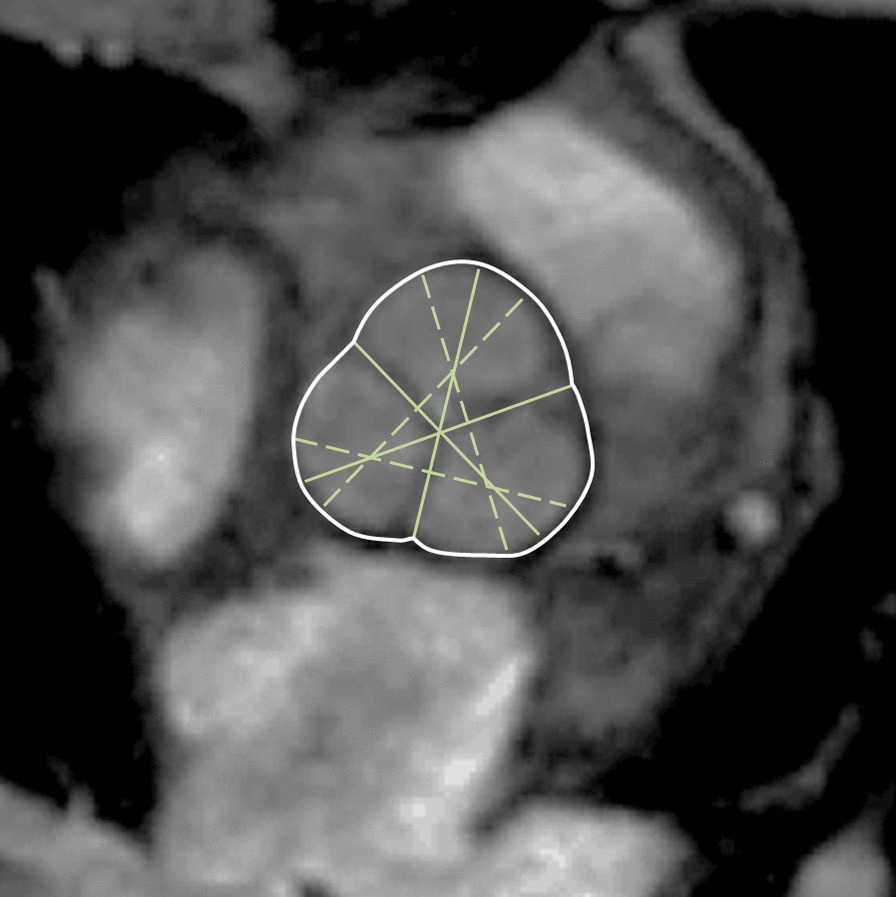

The majority of published articles used semi-automatic software for analysis of LV function and structure [10–16]. Short-axis images are most commonly analyzed on a per-slice basis, deriving LV mass and volume by applying the Simpson’s method (“stack of disks”) [17]. An example of LV contouring is shown in Fig. 1. Automated CMR analysis facilitated by machine learning is rapidly making inroads in LV volume and mass quantification [3]. The primary focus of early manuscripts has been on agreement between manual and automatic contouring [2]. However, to date, CMR variables for healthy cohorts have not been reported using machine learning methods.

Fig. 1.

Contouring of the left ventricle (LV) and right ventricle (RV). Note that LV papillary muscle mass has been isolated and added to LV mass. RV papillary muscles and trabeculations were included in the RV volume